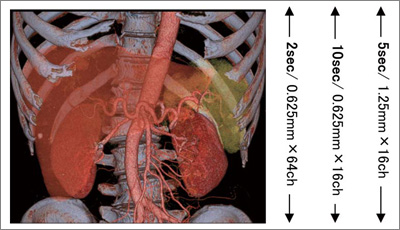

CT装置の進化は著しく,1998年に登場した4列MDCTからわずか6年後の2004年には32列,64列へと進歩を遂げた。MDCTは多列化に伴い,撮影時間の短縮化とともに高い分解能での的確な病変の把握を可能にした。

図1に示すように,64列MDCT「LightSpeed VCT」(以下,VCT)はディテクタが0.625mm×64で構成されているため,40mmのカバレッジを保ちながら0.625mmスライス厚の出力が可能である。医療現場において,ルーチンワークと精査を振り分けることなく検査を行うことができるのは,ワークフローの向上にもつながるであろう |

図1 VCT(64列)とBS Elite(16列)のディテクタ構成 |